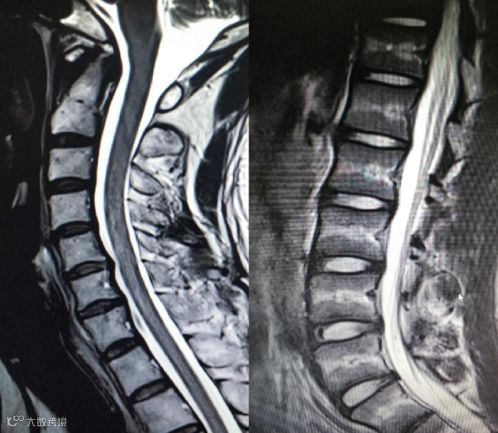

颈椎腰椎——首选MRI,CT次之

MRI能清晰观察椎间盘与相应的神经根及其它软组织,对于关节、肌肉、脂肪组织的检查,亦为首选。

但对于可能选择手术治疗的脊柱疾病,往往需要了解骨骼结构来设计配套的手术方案,这时CT检查也变得非常紧要。